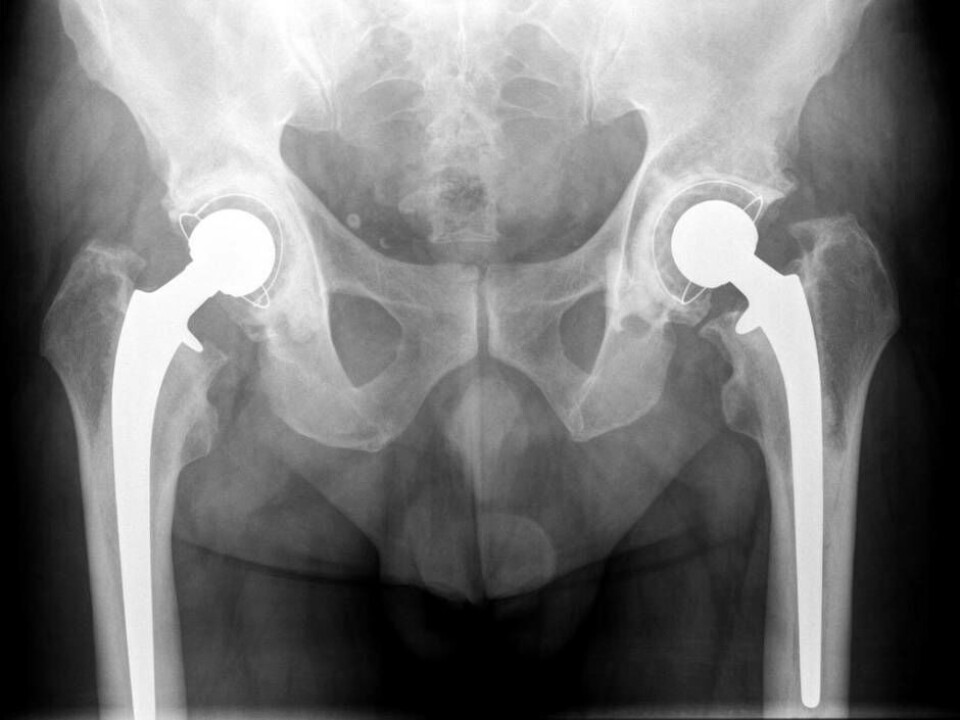

En boende på ett ålderdomshem i Västerås fick en höftfraktur efter ett fall och avled efter en tids vistelse på sjukhus.